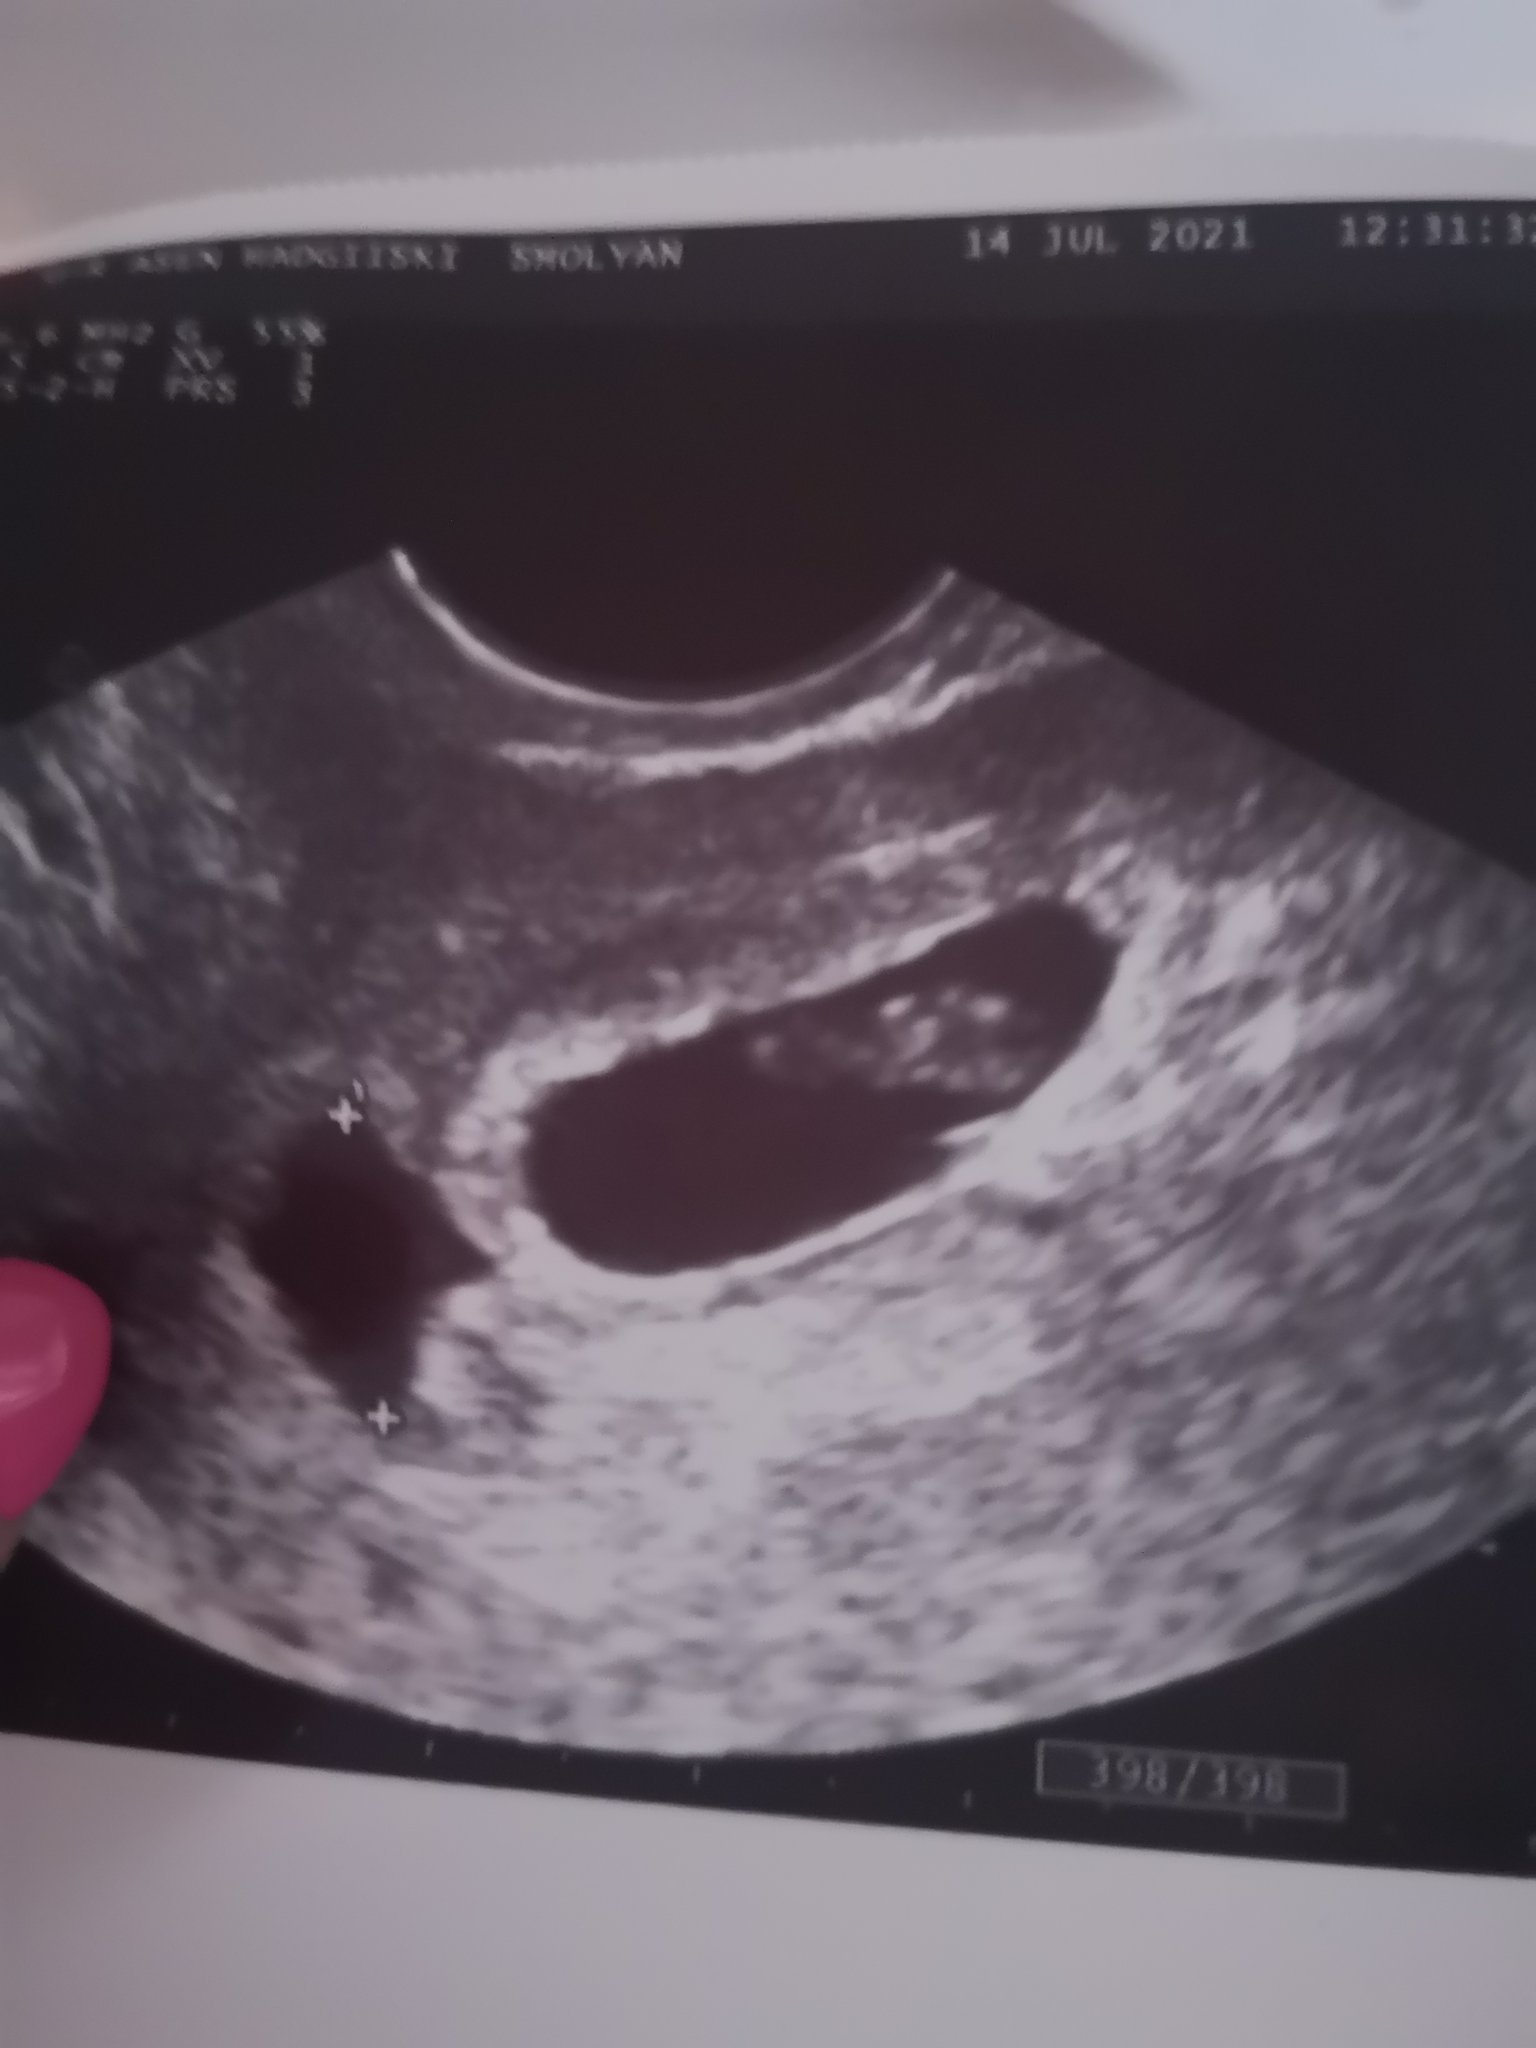

Какви са някои от неразположенията по време на бременност?